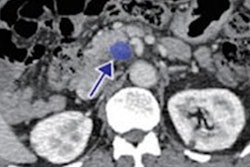

After volumetric segmentation of the pancreas was performed, 88 first-order and gray-level radiomic features were extracted from the CT exams. Ultimately, 34 radiomics features were selected for use by the machine-learning models. The researchers then trained and tested four different classifiers: K-nearest neighbor, support vector machine, random forest, and XGBoost. Two radiologists with nine and three years of post-residency experience, respectively, also evaluated the pancreas in the test set cases on a five-point scale.